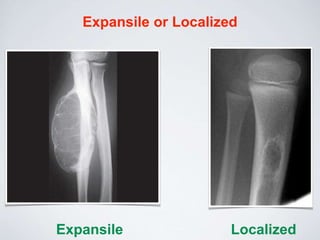

Expansile or Localized

Expansile Localized